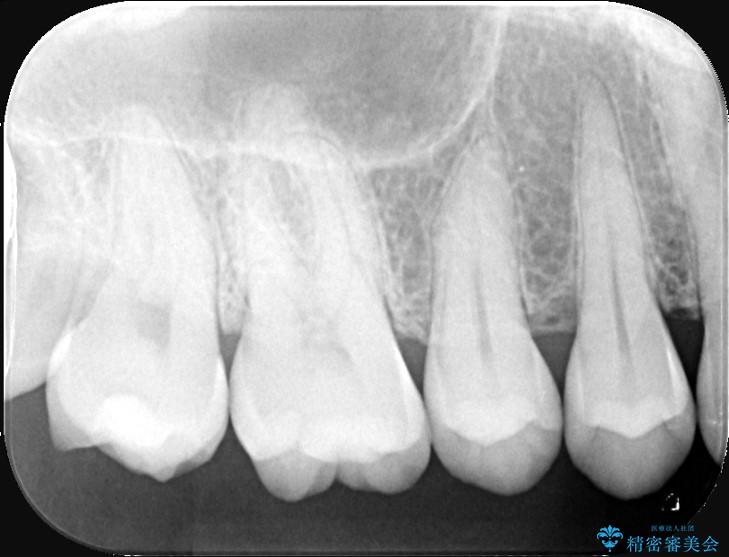

以前に詰めた白い詰め物の内部で、虫歯の再発が確認されました。

まずは古い詰め物と虫歯を丁寧に除去します。